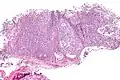

| Micrograph of a myoepithelioma. H&E stain. | |

The myoepithelial cells may be spindled, plasmacytoid, eithelioid or clear. Tubules or epithelium are absent, or present in a small amount (<5%) by definition. Tumours with myoepithelial cells and a large amount of tubules are classified as pleomorphic adenomas (which must also contain the characteristic chondromyxoid stroma, which is normally absent in myoepithelioma).

Low mag.

High mag.